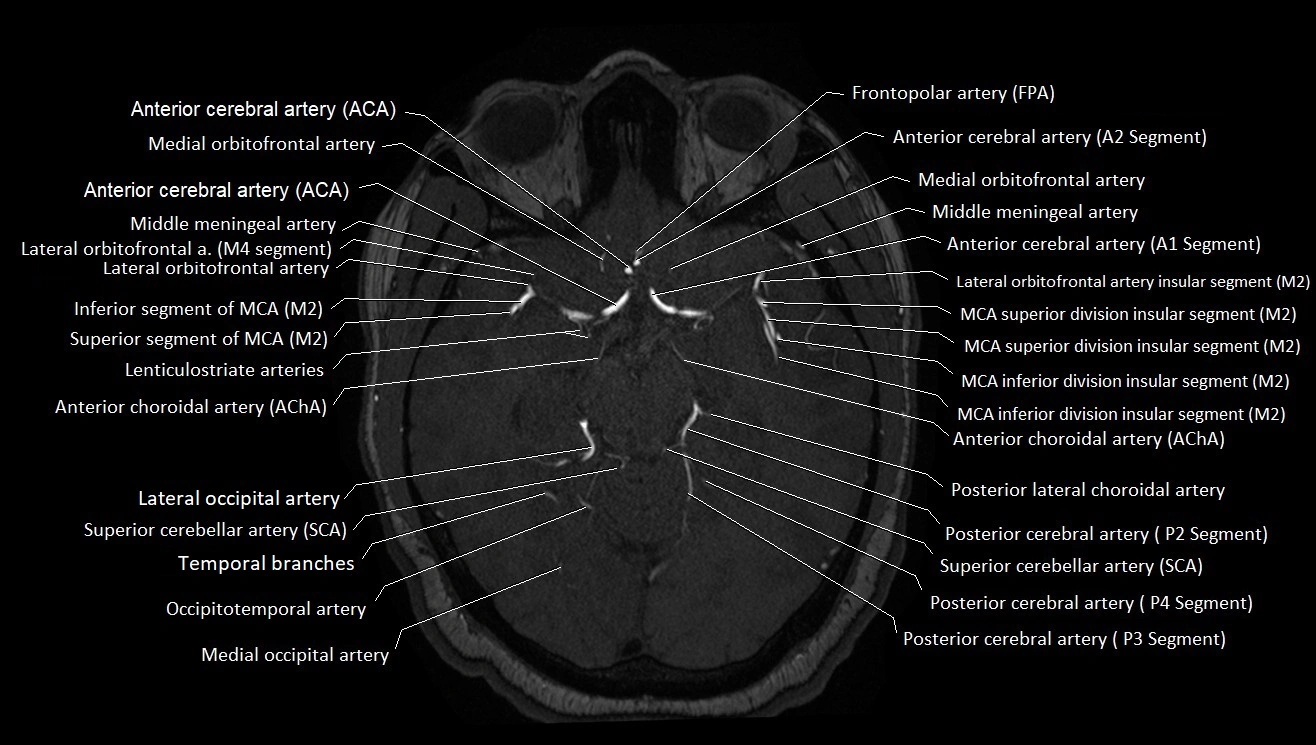

MRI images

image

CT images